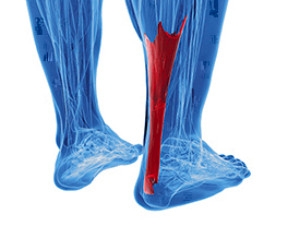

What Happened To My Achilles Tendon?

Patients who have experienced an Achilles tendon injury are familiar with the pain and discomfort that is often associated with it. This tendon connects the heel to the calf muscles, and is considered to be the largest tendon in the body. If it should become inflamed as a result of an injury, Achilles tendonitis may develop. Additionally, it may gradually develop from overuse, and symptoms can consist of pain in the heel area or down the back of the leg. It may feel worse in the morning upon arising, and it will most likely be difficult to flex the foot. Common reasons for this type of injury to occur can include suddenly increasing the intensity of a sporting activity, improper stretching before exercising, or it may come from wearing shoes that do not fit correctly. After a proper diagnosis is performed, the correct treatment can begin which can include a variety of options. If you are afflicted with this condition, it is advised that you consult with a podiatrist who can guide you toward the proper treatment.

Patients who have experienced an Achilles tendon injury are familiar with the pain and discomfort that is often associated with it. This tendon connects the heel to the calf muscles, and is considered to be the largest tendon in the body. If it should become inflamed as a result of an injury, Achilles tendonitis may develop. Additionally, it may gradually develop from overuse, and symptoms can consist of pain in the heel area or down the back of the leg. It may feel worse in the morning upon arising, and it will most likely be difficult to flex the foot. Common reasons for this type of injury to occur can include suddenly increasing the intensity of a sporting activity, improper stretching before exercising, or it may come from wearing shoes that do not fit correctly. After a proper diagnosis is performed, the correct treatment can begin which can include a variety of options. If you are afflicted with this condition, it is advised that you consult with a podiatrist who can guide you toward the proper treatment.

Achilles tendon injuries need immediate attention to avoid future complications. If you have any concerns, contact one of our podiatrists of PA Foot & Ankle Associates. Our doctors can provide the care you need to keep you pain-free and on your feet.

What Is the Achilles Tendon?

The Achilles tendon is a tendon that connects the lower leg muscles and calf to the heel of the foot. It is the strongest tendon in the human body and is essential for making movement possible. Because this tendon is such an integral part of the body, any injuries to it can create immense difficulties and should immediately be presented to a doctor.

There are various types of injuries that can affect the Achilles tendon. The two most common injuries are Achilles tendinitis and ruptures of the tendon.

Achilles Tendinitis Symptoms

- Inflammation

- Dull to severe pain

- Increased blood flow to the tendon

- Thickening of the tendon

Rupture Symptoms

- Extreme pain and swelling in the foot

- Total immobility

Treatment and Prevention

Achilles tendon injuries are diagnosed by a thorough physical evaluation, which can include an MRI. Treatment involves rest, physical therapy, and in some cases, surgery. However, various preventative measures can be taken to avoid these injuries, such as:

- Thorough stretching of the tendon before and after exercise

- Strengthening exercises like calf raises, squats, leg curls, leg extensions, leg raises, lunges, and leg presses

What are Achilles Tendon Injuries

The Achilles tendon is the strongest tendon in the human body. Its purpose is to connect the lower leg muscles and calf to the heel of the foot. This tendon is responsible for facilitating all types of movement, like walking and running. This tendon provides an enormous amount of mobility for the body. Any injuries inflicted to this tissue should be immediately brought up with a physician to prevent further damage.

The most common injuries that can trouble the Achilles tendon are tendon ruptures and Achilles tendinitis. Achilles tendinitis is the milder of the two injuries. It can be recognized by the following symptoms: inflammation, dull-to-severe pain, increased blood flow to the tendon, thickening of the tendon, and slower movement time. Tendinitis can be treated via several methods and is often diagnosed by an MRI.

An Achilles tendon rupture is trickier to heal, and is by far the most painful injury. It is caused by the tendon ripping or completely snapping. The results are immediate and absolutely devastating, and will render the patient immobile. If a rupture or tear occurs, operative and non-operative methods are available. Once the treatment begins, depending on the severity of the injury, recovery time for these types of issues can take up to a year.

Simple preventative measures can be taken as a means to avoid both injuries. Prior to any movement, taking a few minutes to stretch out the tendon is a great way to stimulate the tissue. Calf raises, squats, leg curls, leg extensions, leg raises, lunges, and leg presses are all suggested ways to help strengthen the lower legs and promote Achilles tendon health.

Many problems arise among athletes and people who overexert themselves while exercising. Problems can also happen among those who do not warm up properly before beginning an activity. Proper, comfortable shoes that fit correctly can also decrease tendon injuries. Some professionals also suggest that when exercising, you should make sure that the floor you are on is cushioned or has a mat. This will relieve pressure on the heels. A healthy diet will also increase tendon health.

It is very important to seek out a podiatrist if you believe you have an injury in the Achilles region. Further damage could result in severe complications that would make being mobile difficult, if not impossible.